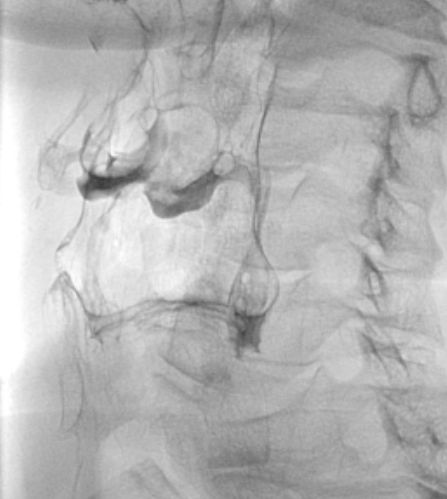

Kontrastdarstellung des normalen Sinus piriformis